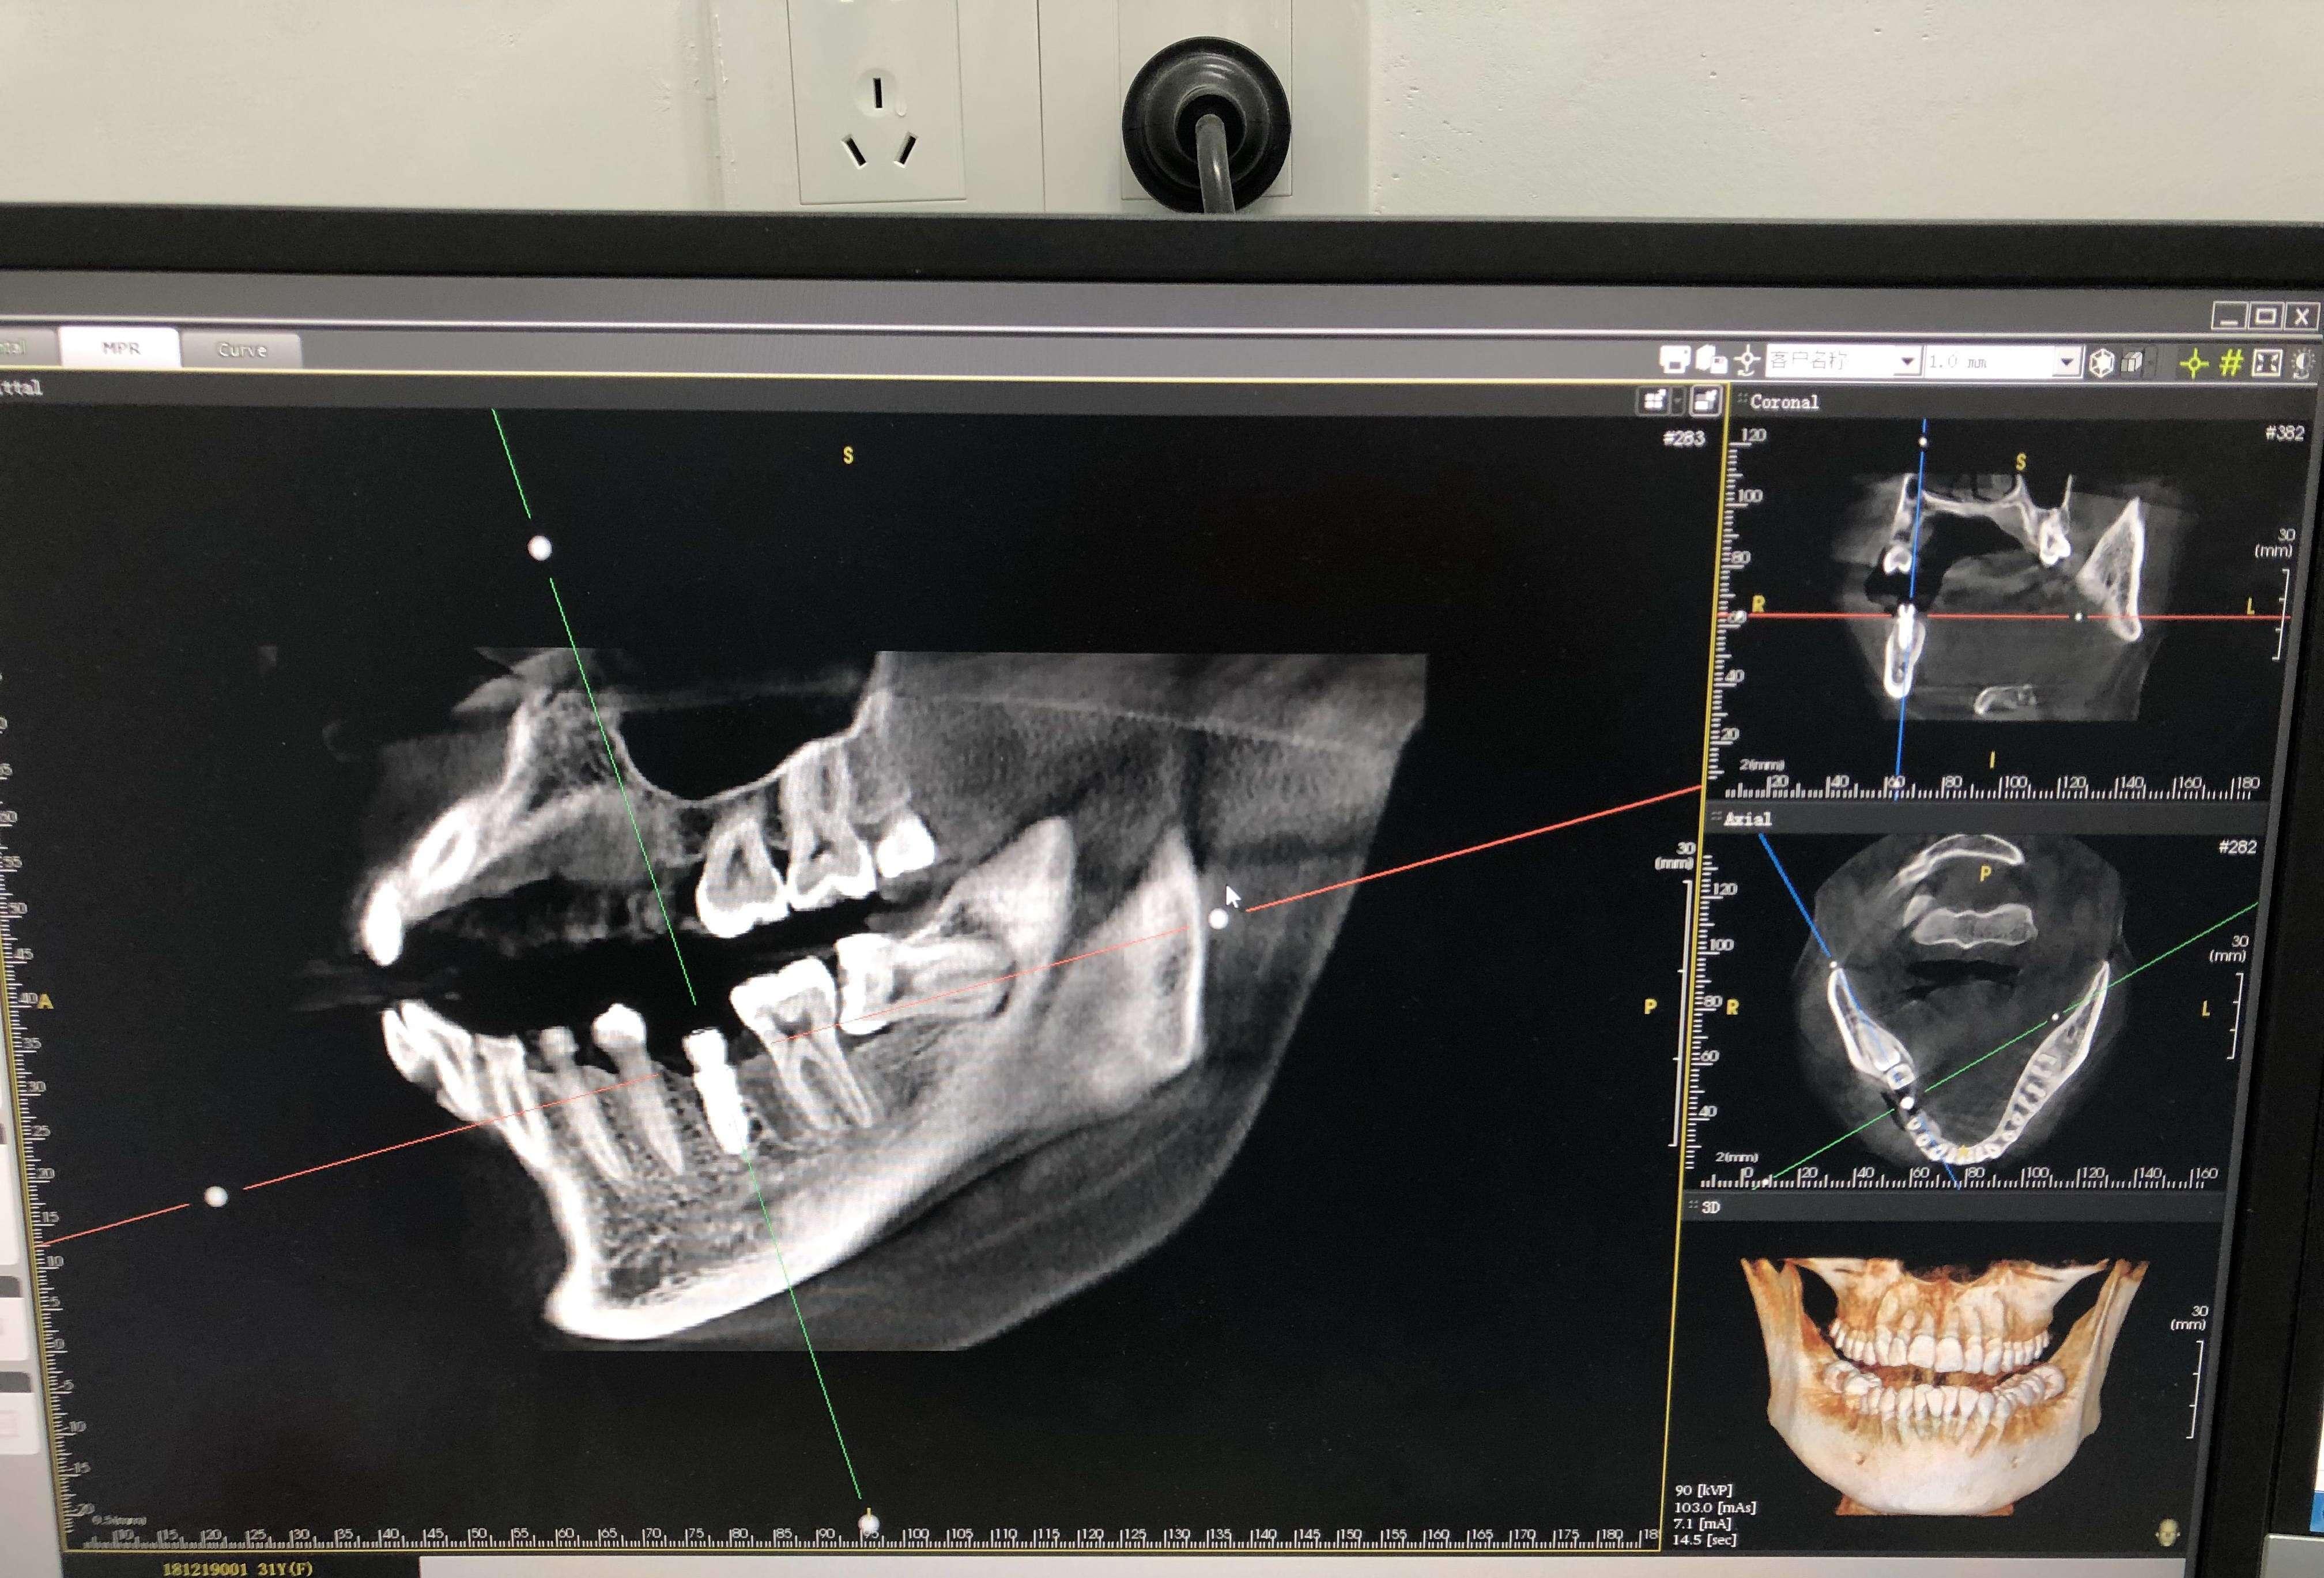

值得关注的是,科瓦口腔还汇聚了包括韩国种植专家姜信模等在内的国外权威口腔专家定期坐诊,引进高端原装进口舒适化牙科综合治疗椅、韩国进口三维口腔CT、进口WH种植机等数字化口腔医疗设备。

在技术层面上,科瓦口腔掌握数字化精准医疗技术,以家庭式服务温暖每一位顾客,门诊医生秉承匠心精神和严谨的医学态度为每一个家庭每一位患者负责,科瓦口腔致力于打造家庭护齿计划,让海宁乃至周边城市的每个家庭都拥有自己的护齿管家,从齿提高幸福指数,一口好牙享受品质生活。